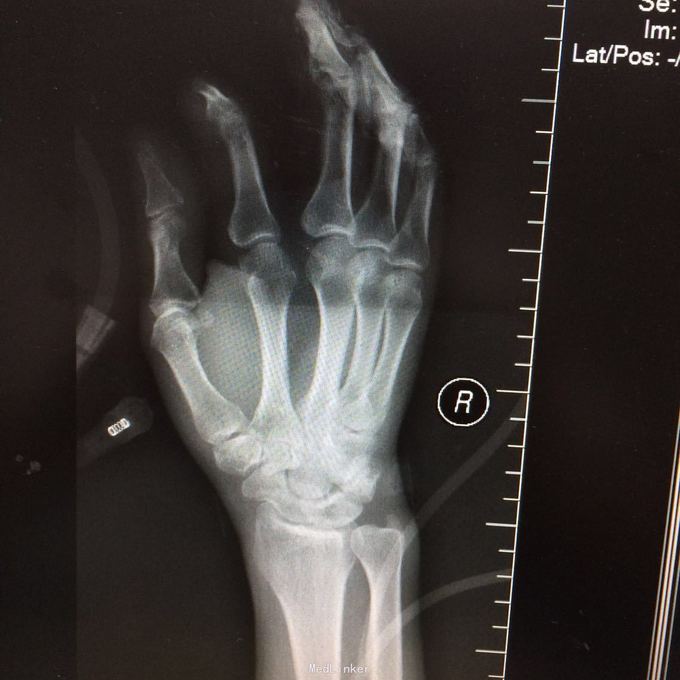

患者某某,男,49岁,因“高处坠落致全身多处疼痛、肿胀、流血2小时 1、男性壮年患者。 2、缘患者于2小时前因高处坠落致左肘、左手、右手、头面部、左胸,左足等多处受伤,即觉左肘部疼痛、活动困难、流血;左手、头面部伤口疼痛、流血;右手、左胸,左足部等处疼痛、肿胀。由家属、同事送往我院就诊,经行X线检查示:左肱骨远端粉碎性骨折,左肘关节半脱位;左手第4、5掌骨远端骨折;右手第1远节指骨基底部、第3、4远节指骨骨折,第5中节、远节指骨骨折;左跟骨粉碎性骨折。CT示:鼻中隔骨折;右侧第3--7肋骨折。急诊科予清创包扎止血,为作进一步诊治而收入院。患者受伤以来,患者精神好,无呼吸困难,无恶心、呕吐,无头晕,无面色苍白,无双下肢麻木、无力,无大小便失禁。 3、查体:T36.8 ℃ P 76次/分 R20 次/分 BP104/67mmHg。神清合作、应答切题、全身皮肤粘膜无黄染、浅表淋巴结无肿大。头颅五官无畸形,左眉弓处见一长约2cm伤口,活动性出血,巩膜无黄染,双侧瞳孔等大等圆,直径 3 mm,对光反射灵敏。鼻梁有一长约3cm纵行伤,深及皮下,伴有活动性出血;下唇部见一1*1cm组织缺损,伴活动性出血.颈软,无抵抗,气管居中,甲状腺无肿大,胸廓无畸形,右侧胸部局部压痛明显,胸廓挤压征阳性;心前区无隆起,双肺叩诊清音,呼吸音清,无干湿性罗音。心率76次/分,律齐有力,各瓣膜区无病理性杂音。腹平,腹肌软,全腹压痛、无反跳痛,肝脾肋下未及,双肾区无叩痛,无移动性浊音,肠鸣音存在,4-6次/分。脊柱、骨盆无压痛,四肢检查详见专科情况,其余肢体检查正常。双下肢生理反射存在,病理性反射未引出。

4、专科情况:左肘部中度肿胀,呈短缩、成角畸形,局部皮肤活动性出血,局部压痛明显,纵向叩击痛,左肘部可扪及骨擦感,有反常活动,左肘部活动障碍。左肩峰至肱骨外上髁上臂长度较右侧短缩1厘米,左手掌尺侧轻度肿胀,无畸形,局部皮肤正常,局部压痛明显,可扪及骨擦感,无反常活动,左手指活动正常。左侧手指肌力Ⅳ级,有牵拉痛,左上肢手指末梢血运良好,感觉略差。右手拇指、环指及尾指局部皮肤组织撕脱,渗血明显;右手中指末端损毁,局部缺失。右手手指肌力Ⅳ级末梢血运良好。左足跟部肿胀明显,局部皮肤正常,局部压痛明显,纵向叩击痛,左足跟部可扪及骨擦感,左足趾肌力Ⅳ级,无牵拉痛,左足趾末梢血运及感觉良好。 5、辅助检查:本院2015年11月14日X线检查示:左肱骨远端粉碎性骨折,左肘关节半脱位;左手第4、5掌骨远端骨折;右手第1远节指骨基底部、第3、4远节指骨骨折,第5中节、远节指骨骨折;左跟骨粉碎性骨折。CT示:鼻中隔骨折;右侧第3--7肋骨折;左下肺挫伤。